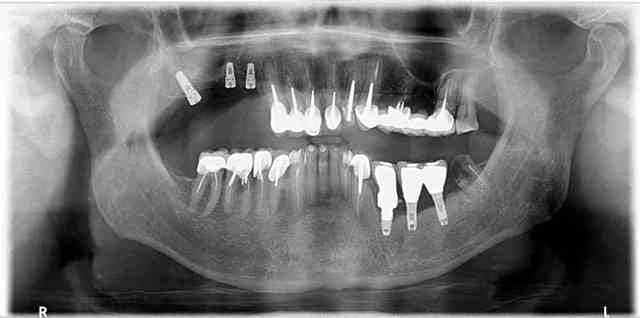

Et pour illustrer mes propos voici quelques photos issus du book of horror que je suis en train de me constituer.

Quand vous tombé là-dessus, quelle est votre réaction? Et surtout quand ça a été commis dans votre propre cabinet pour une somme indécente. Le patient vous demande de finir le travail alors qu'il a déjà dépenser une fortune pour ce résultat. Et il faut prendre en compte le fait que des patients dans cet état j'en ai des dizaines elle que le gars qui a fait ça n'a en aucun cas l'intention de rembourser quoi que ce soit.

Vous voyez, on est loin du niti pété ou de la couronne débordante... Et le monsieur est expert devant les tribunaux...